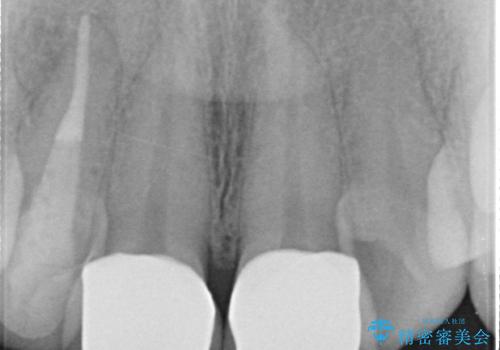

- 上顎前歯の見た目が気になるのでセラミックにしたいといらっしゃった方の症例です。

右上2は歯の神経が死んでおり、根尖病変を認めたため根管治療を行いました。

その後右上1,2番目及び左上1番目の歯に対してオールセラミッククラウンによる補綴を行いました。